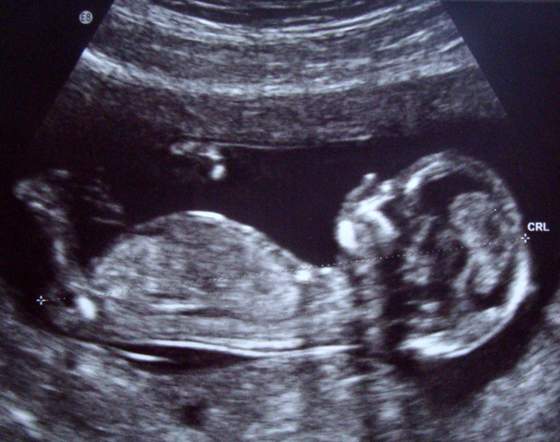

Błonka cudne to Wasze maleństwo!!! GratulujęWszystko widać elegancko - nosek, uszko, usteczka, odjazd!

Macie jakieś info o płci?

aia slicznoscichyba dziewczynka co?